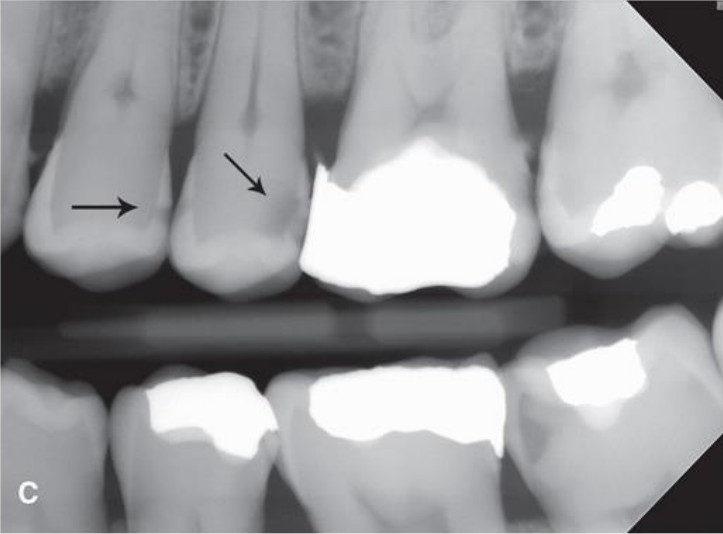

caries or cervical burn out

burnout

caries or cervical burnout

caries